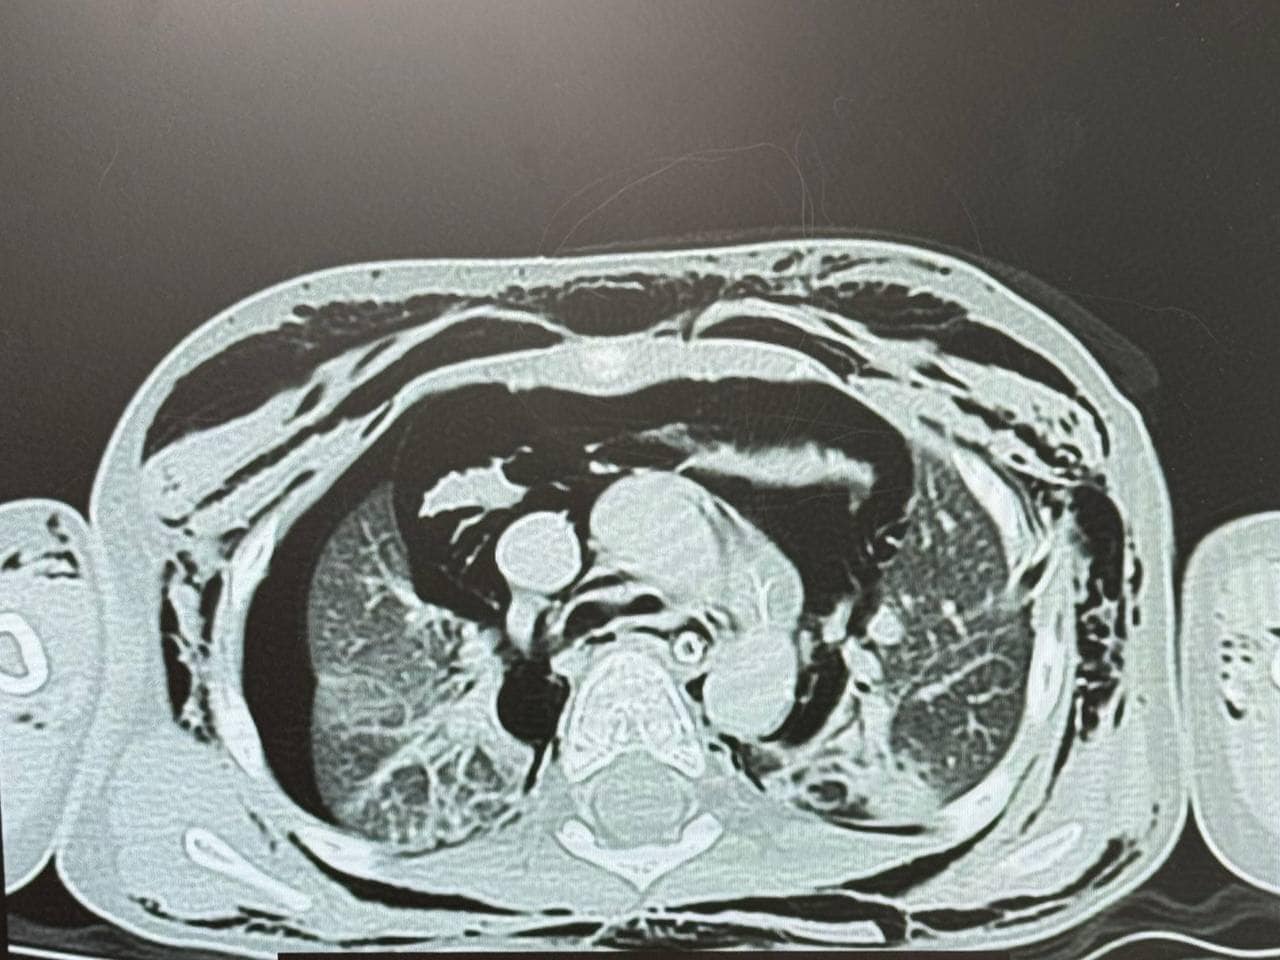

У рідному місті, де Луку під час стоматологічного лікування інтубували, мама хлопчика помітила, що у сина почало боліти горло, з'явилися набряки на шиї, голові та обличчі, а дихання стало утрудненим. Термінове звернення до місцевої лікарні виявило накопичення повітря в середостінні, під шкірою голови, шиї та грудної клітки, що свідчило про порушення цілісності дихальних шляхів.

Луку терміново доставили до «Охматдиту», де спеціалісти виявили розрив трахеї довжиною 2,5-3 см. Того ж дня була проведена операція, під час якої медики успішно зашили і відновили цілісність трахеї.

Дитячий хірург Євген Руденко пояснює, що розрив трахеї є небезпечним через те, що повітря, яке виходить за межі дихальних шляхів, накопичується в середостінні під тиском. Це може призвести до стискання внутрішніх органів – серця і легень, що, в свою чергу, може викликати дихальну недостатність або навіть загрозу життю.